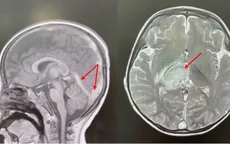

VTV.vn - Nữ bệnh nhân 37 tuổi bị đau đầu dữ dội, suy giảm ý thức được Bệnh viện Đa khoa Hà Giang (Tuyên Quang) điều trị thành công ca huyết khối xoang tĩnh mạch não nguy hiểm.